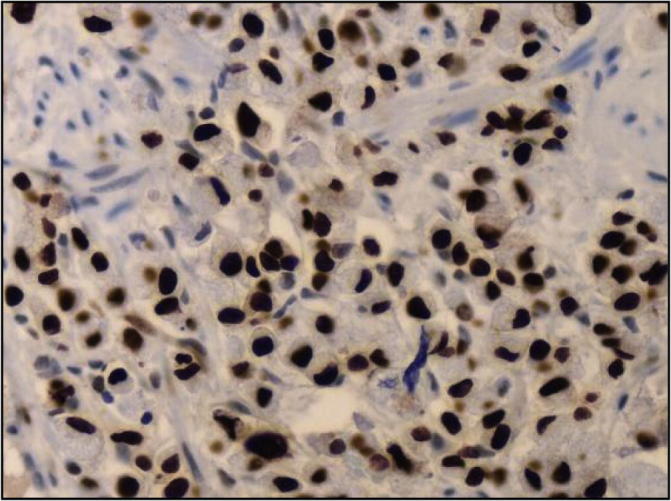

The distribution of the Ki-67 labeling index as measured by the percentage of positively stained cells is shown in Fig. 2, Fig. 3, Fig. 4, Fig. 5. Positive immunoperoxidase reaction in the Ki-67 antibody-stained sections was confined to the nuclei of carcinoma cells (Fig. 2) and was found to be expressed in 89/92 of the studied tissue samples. The proportion of Ki-67 positive cells in breast carcinomas varied from 0.8% to 70% (median, 7.5%). while 3 cases were completely negative for Ki-67 expression. Ki-67 scores counted by two independent pathologists (study Pathologists) were in good agreement. 33 cases had a value of 10–19% on the Ki-67 index (Fig. 3), 36 cases had value >20 and <50% (Fig. 4) and 20 cases had a value >50% (Fig. 5). The breast biopsy proved to be benign lesion by histopathology, there was no need to perform immunoreactivity to Ki-67 expression.

Fig. 2.

Nuclear immunohistochemical staining for Ki-67 in invasive breast carcinoma (Avidin-biotin-peroxidase complex (ABC) immunoperoxidase + Diaminobenzidine (DAB) chromogen × 400).